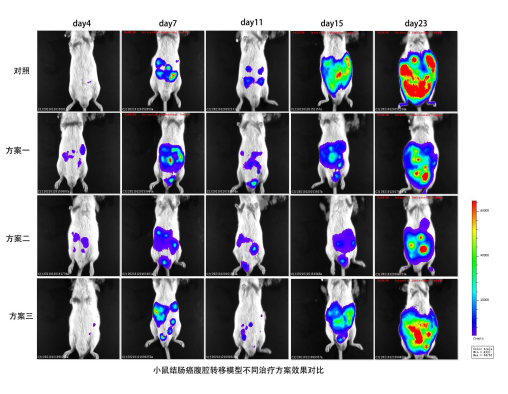

1.不同治疗方案对小鼠结肠癌腹腔转移模型的效果比较